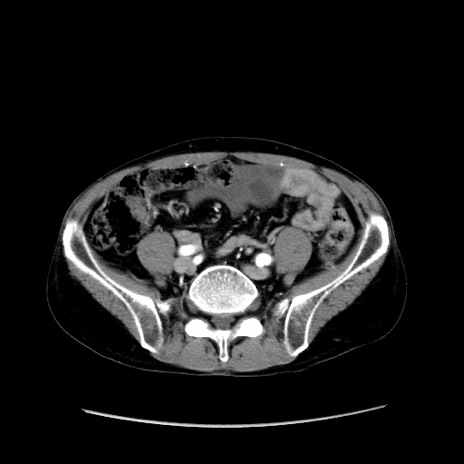

症例37(横断像)

【症例】40歳代 男性

【主訴】腹痛

【現病歴】4時間ほど前に電車に乗車中に臍部上より腹痛出現。徐々に増悪し起立困難となり、救急外来受診。生ものは数日食べていない。今朝お雑煮を食べた。

【身体所見】BT 36.8℃、BP 117/84mmHg、HR 91/min、SpO2 97%、苦悶様、腹部:臍上部広範囲圧痛あり、反跳痛±

【データ】WBC 8100、CRP 0.03